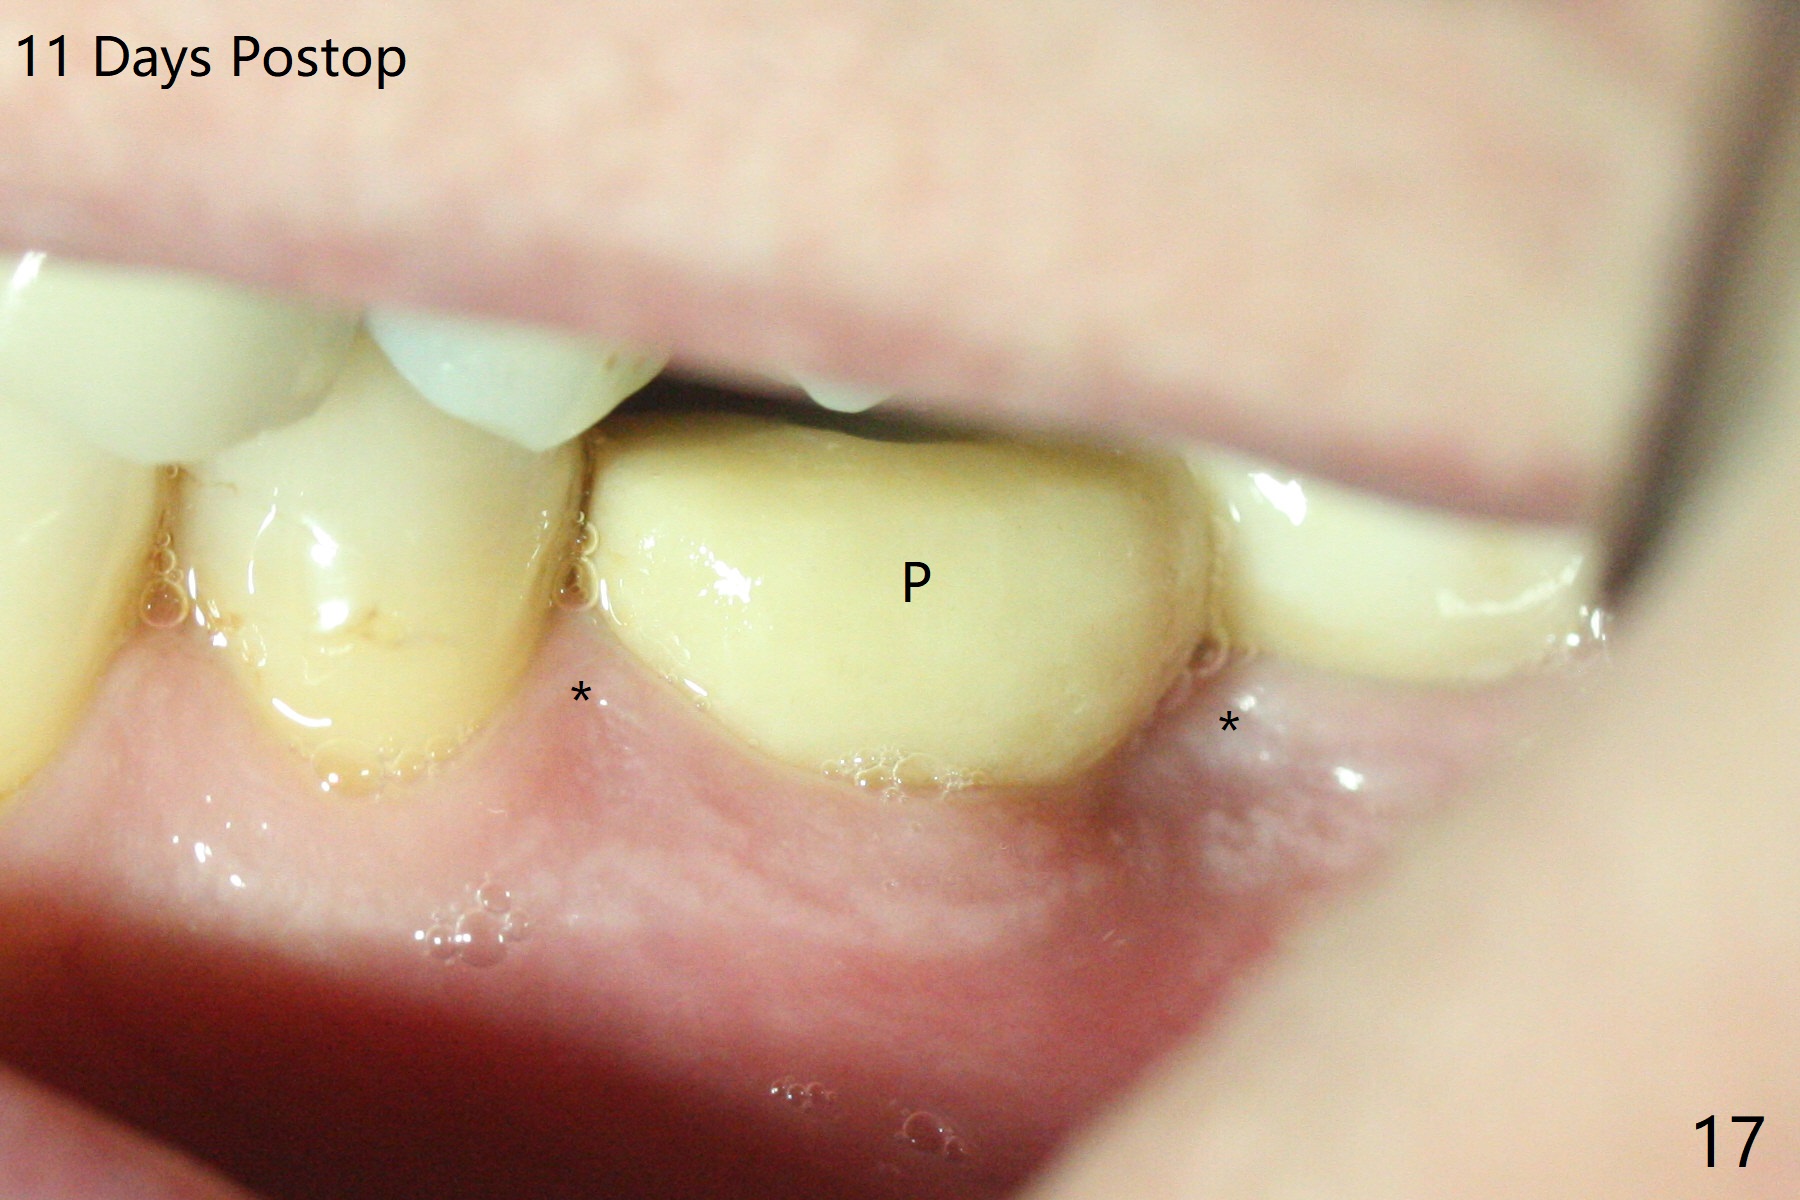

Venopuncture is conducted (Fig.1) for PRF and sticky bone (cortical chip and .5 cc ß-TCP). After use of proximators at #19, cowhorn forceps are applied, resulting in metal crown dislodgement. Since there is distal bone loss, distal socket sheath is contemplated. The tooth is sectioned. When an elevator is inserted between the roots, the distal root is loosened first. The 2 roots are removed, revealing a rounded end septum (Fig.2 S) and a larger distal socket. To avoid osteotomy deviation over the septum, a 12 mm bone trimmer is used, followed by point drill (Fig.3 *). But the lower half of the implant is deviated mesial (Fig.4) with decreased torque (~ 10 Ncm). To overcome this misfortune, the roots should not be removed until osteotomy is finished. Dual zones of bone graft is conducted. Sticky bone is placed until the plateau of the implant with a healing screw in place (Fig.4 * (bone zone)). After placement of a pair abutment, the same bone graft is packed until the margin of the abutment (Fig.5 * (soft tissue zone)). An immediate provisional is fabricated to close the socket with a piece of PRF as well. Fig.6-11 explains why the lower half of the implant deviates to the mesial socket, while Fig.12-16 illustrates how to prevent the deviation. After extraction of #19 (Fig.6,7), the crest of the septum is flattened (Fig.8 arrowhead) to prevent the initial deviation (Fig.9 red line). When a drill reaches a space (a socket, mesial in this case), the drill is deflected to the least resistant area (Fig.10 a bent red line), leading to the implant deviation apically (Fig.11 green). To prevent the apical deviation, therefore, the roots of the affected tooth is temporarily not removed (Fig.12). The osteotomy should not deviates with surgical guide because of similar density between the tooth and the bone (Fig.13). When the osteotomy is finished (Fig.14), the roots are extracted (Fig.15). The implant to be placed should not have deviation (Fig.16 green). The papillae are maintained by the immediate provisional 11 days postop (Fig.17). The incompletely seated abutment at #18 (Fig.5 <) is reseated completely 6 months postop (Fig.18). Crestal bone forms distal to #19 implant. There is no bone loss 4 months and 3 years 1 month post cementation at #19 and 18, respectively (Fig.19,20).